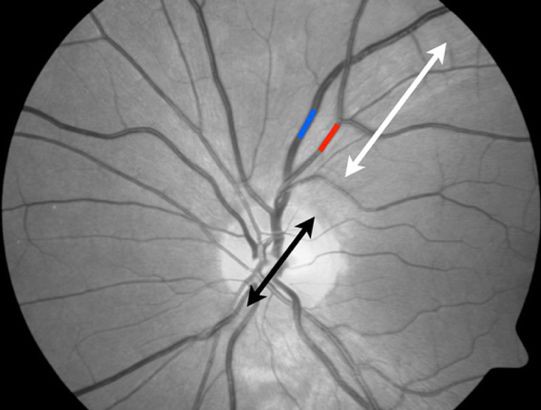

De Maastrichtse onderzoekers volgden gedurende vier jaar bijna drieduizend mensen tussen de 40 en 75 jaar die aan het begin van de studie geen tot weinig symptomen hadden van depressie. Bij hen werd de functie van de kleine bloedvaten in kaart gebracht: in de huid, in het oog (meer precies in het netvlies) en met biomarkers uit het bloed. Die metingen zijn bijzonder. Schade aan de grote vaten is relatief gemakkelijk vast te stellen, maar het in beeld brengen van de functie van de haarvaten is veel lastiger. Het vergt veel training en ervaring van de onderzoeker, is arbeidsintensief, tijdrovend, kostbaar en er is geavanceerde apparatuur nodig.